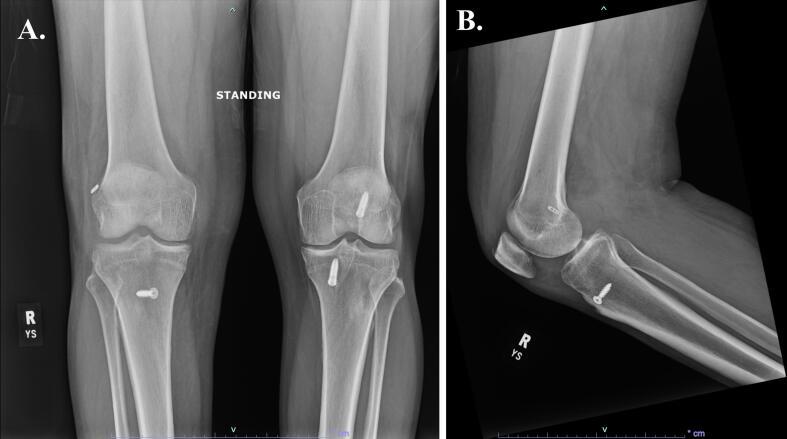

This clinical case report presents a 40-year-old male who sustained an ipsilateral hip and knee dislocation with ipsilateral femoral head fracture and incomplete femoral neck fracture following a motorcycle collision.

本临床病例报告介绍了一名40岁男性,该患者在摩托车碰撞后发生同侧髋部和膝部脱位,并伴有同侧股骨头骨折和股骨颈不完全骨折。